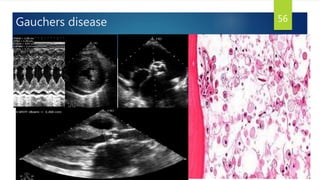

Gauchers disease 56